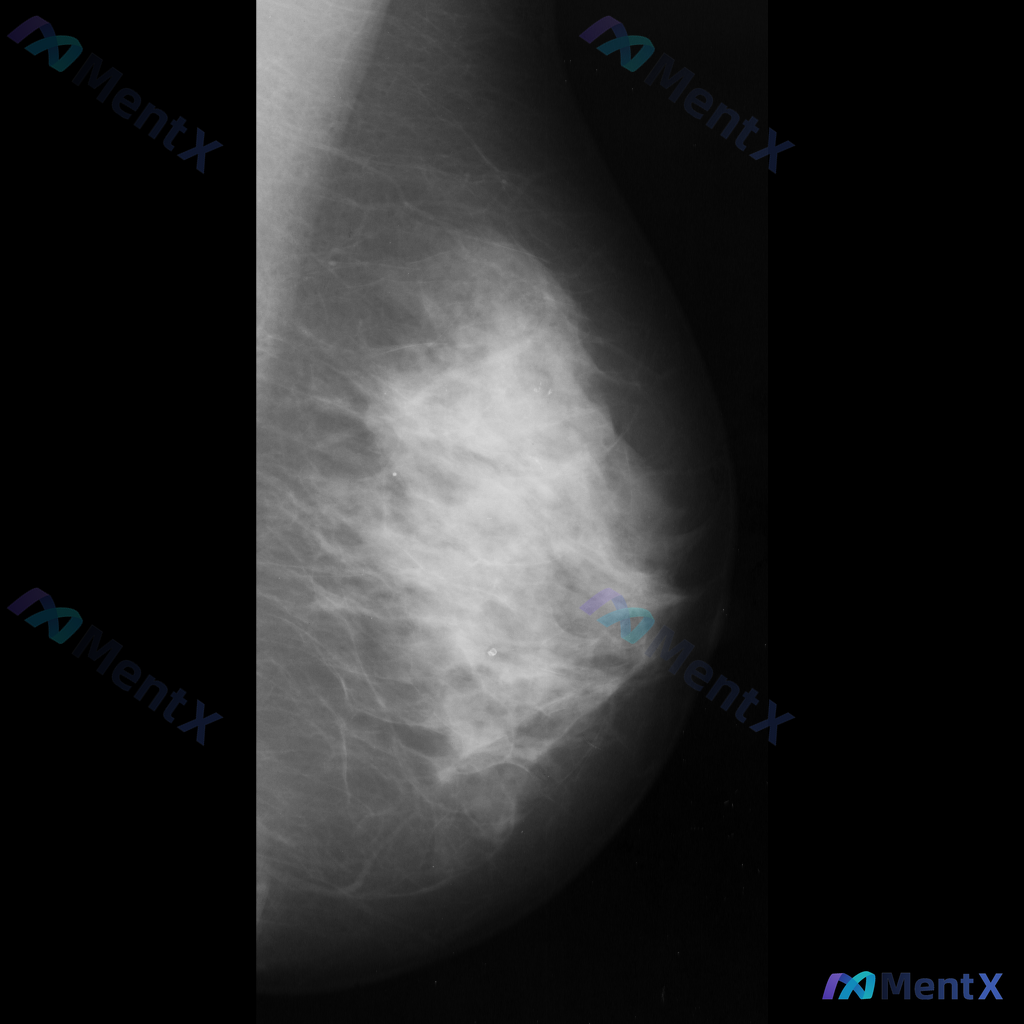

左侧乳腺钼靶见局限性结构扭曲,无明确肿块钙化,你会先考虑哪类情况?

整理到一份乳腺钼靶的影像资料,想和大家讨论一下: - 钼靶所见:左侧乳腺中央偏下区域存在局限性结构扭曲,表现为纤维腺体组织排列紊乱、牵拉;未见明确的肿块或钙化灶。 - 背景:乳腺密度较高,属于不均匀致密型或极度致密型(ACR B或C型)。 目前这种结构扭曲的表现,大家会先往哪个方向考虑?下一步的评估...

整理到一份单侧乳腺钼靶的影像资料,想和大家讨论一下读片思路: 影像背景与征象 - 背景:不均匀致密型乳腺 - 主要异常: 1. 乳腺中央及中下部可见一片边界模糊的斑片状/不规则形密度增高区 2. 该密度增高区域内,似乎存在乳腺正常小梁结构的牵拉或紊乱 3. 中下部偏乳头方向,有一组较为集中的、形态不...